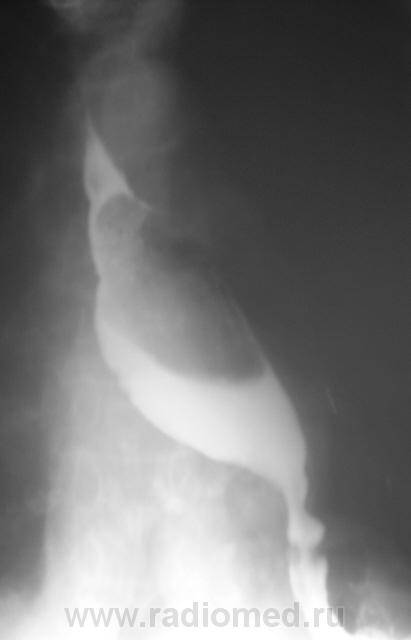

Далее исследование было продолжено в положении лёжа.

ахалазия пищевода...

Похоже что в нижней трети пишевода чтото "живёт"

Озлокачествленная лейомиома пищевода.

Ну, лейомиому, мы написали в протоколе.